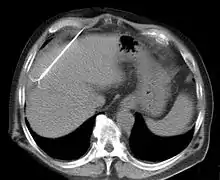

CT scan showing radiofrequency ablation of a liver lesion

RFA may be performed to treat tumors in the lung,[6][7][8] liver,[9] kidney, and bone, as well as other body organs less commonly. Once the diagnosis of tumor is confirmed, a needle-like RFA probe is placed inside the tumor. The radiofrequency waves passing through the probe increase the temperature within tumor tissue and results in destruction of the tumor. RFA can be used with small tumors, whether these arose within the organ (primary tumors) or spread to the organ (metastases). The suitability of RFA for a particular tumor depends on multiple factors.